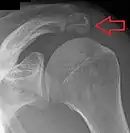

Shoulder

- An os acromiale forms when any of its four ossification centers fail to fuse. These four ossification centers are called (from tip to base) pre-acromion, meso-acromion, meta-acromion, and basi-acromion. In most cases, the first three fuse at 15–18 years, whereas the base part fuses to the scapular spine at 12 years. Such failure to fuse occurs in between 1% and 15% of cases.[23][24] It rarely causes pain.